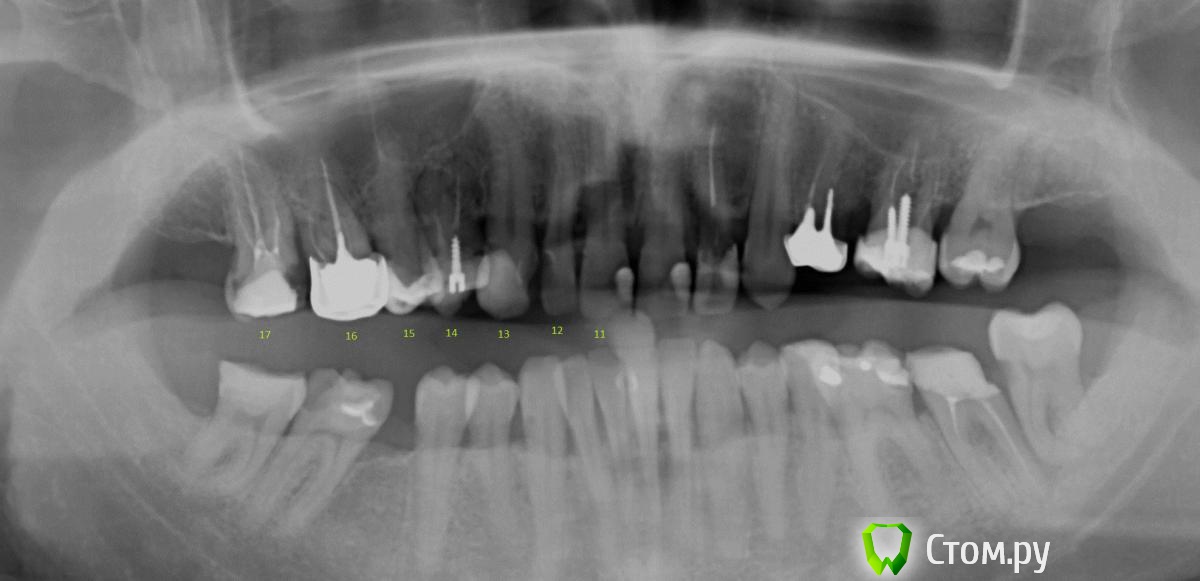

Вася123 Опубликовано 27 марта, 2014 Поделиться Опубликовано 27 марта, 2014 Добрый деньПоделитесь пожалуйста мыслями. Интересует только то что на фото. На фото изображена верхняя челюсть, правая часть, зубы 13 - клык, живой, пломба14,- штифт, пломба15,- пломба16, - вкладка + коронка17. - пломба врач одной из частных клиник рекомендует:14 зуб удалить, т.к. именно над ним он заметил воспаление костной ткани13 и 15 депульпация и обточка то ли под мост то ли под протез на место 14го16 зуб не удалять, тк воспаления нет, а просто перепломбировать каналы + замена коронки17 зуб - под коронку врач другой частной клиники рекомендует16 зуб удалить и тоже что то про протезы советовал Мало того что это все стоит очень прилично, у меня нет уверенности что сделают все это:- во первых по правильной схеме,- во вторых качествено..- не навредят еще больше Подскажите насколько адекватно мнение врачей ? Нужно ли вобще чтото удалять?Если и правда есть воспаление костной ткани - насколько это страшно и что с этим делать? Ссылка на комментарий

DmitrySH Опубликовано 27 марта, 2014 Поделиться Опубликовано 27 марта, 2014 Тут конечно смотреть в полости рта, что там с зубом 14. То, что вокруг зуба изменения - еще не повод для удаления. Примерный план такой:17, 16, 14 ревизия каналов и покрытие коронками, 15, 13 лечение и восстановление исходя из размера поражения Если 14 удаляется, то имплантация. Не надо мосты городить. P.S. все остальные зубы верхней челюсти и нижние моляры тоже требуют к себе внимания. Заниматься частичным латанием дыр уже поздно, требуется комплексная реабилитация Ссылка на комментарий

DmitrySH Опубликовано 28 марта, 2014 Поделиться Опубликовано 28 марта, 2014 Не могли бы Вы про остальные зубы (если из снимка чтото можно понять конечно) рассказать что делать (по номерам)?? 11, 21 - лечение кариеса, (коронки ?)22 - вкладка и коронка23 - лечение кариеса24 - Неважно выглядит на снимке, нужно смотреть в полости рта. 26,37 - ревизия каналов, кладка и коронка38 - удаление36,47 - Пломба или керамическая накладка/коронка ( после осмотра в полости рта)48 - ? тоже нужно смотреть как-то так Ссылка на комментарий